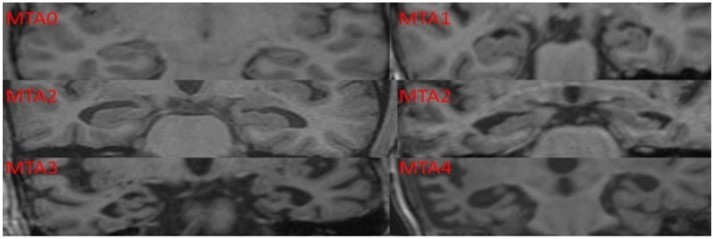

Scheltens Visual Rating of Medial Temporal Lobe Atrophy: The visual rating of MTLA was done using this scale5by obtaining T1 weighted coronal section image on MRI scan of the brain. This rating does not require any special radiological training and can be done easily using hard copies of T1 weighted coronal sections of the brain

MRI. It has a diagnostic accuracy of over 80% in diagnosing dementia of Alzheimer’s type (Table 1).

Table 1. Methodology of Scheltens Visual Rating for Medial Temporal Rating Scale| Scoring | Interpretation |

| 0 | No atrophy |

| 1 | Minimal atrophy |

| 2 | Mild atrophy |

| 3 | Moderate atrophy |

| 4 | Severe atrophy |

MTLA was assessed using a template based on Scheltens Visual Rating Scale (Figure 1). MRI scans were done using 1.5 Tesla Magnetic Resonance (Megnatom Symphony 1.5T scanner). T1 weighted Coronal sections were used for rating MTLA.

Figure 1.Scheltens Visual Rating Scale used in the current study to assess the medial temporal lobe atrophy rating scores.